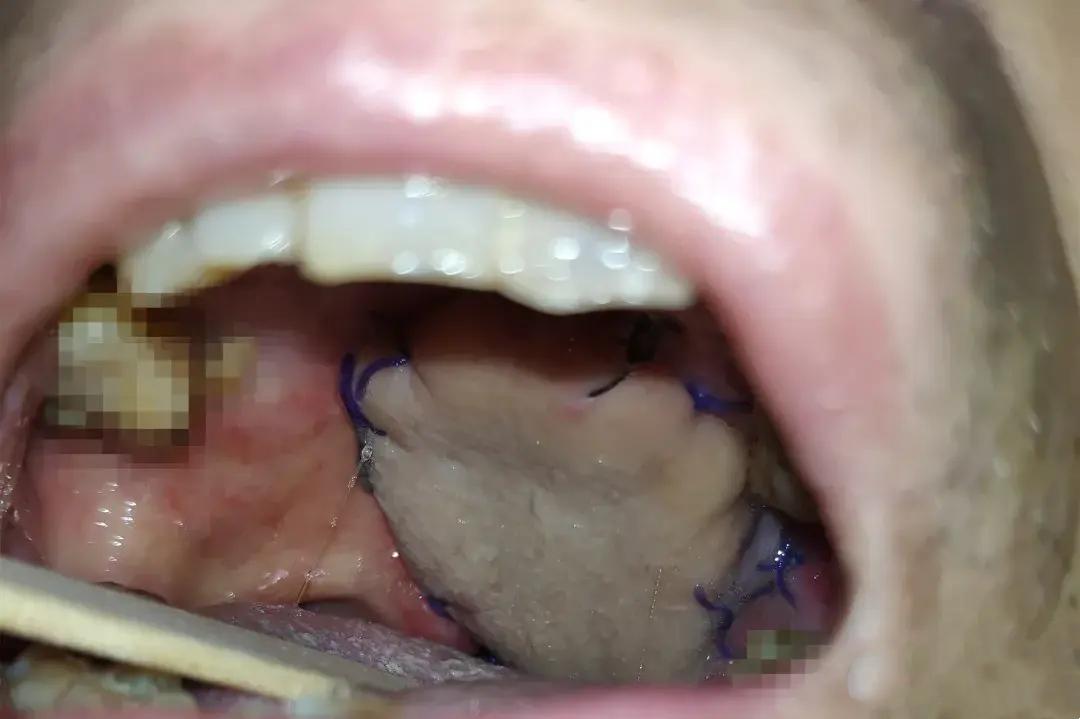

郑州张先生坚持喝热水养生20年,却因舌部菜花样溃疡确诊早期舌癌。医生指出,65℃以上热饮被世卫组织列为2A类致癌物,长期热刺激会损伤口腔黏膜,反复修复中细胞易癌变。健康饮水需控制温度,40℃左右温水更适宜。多喝热水对身体好吗?